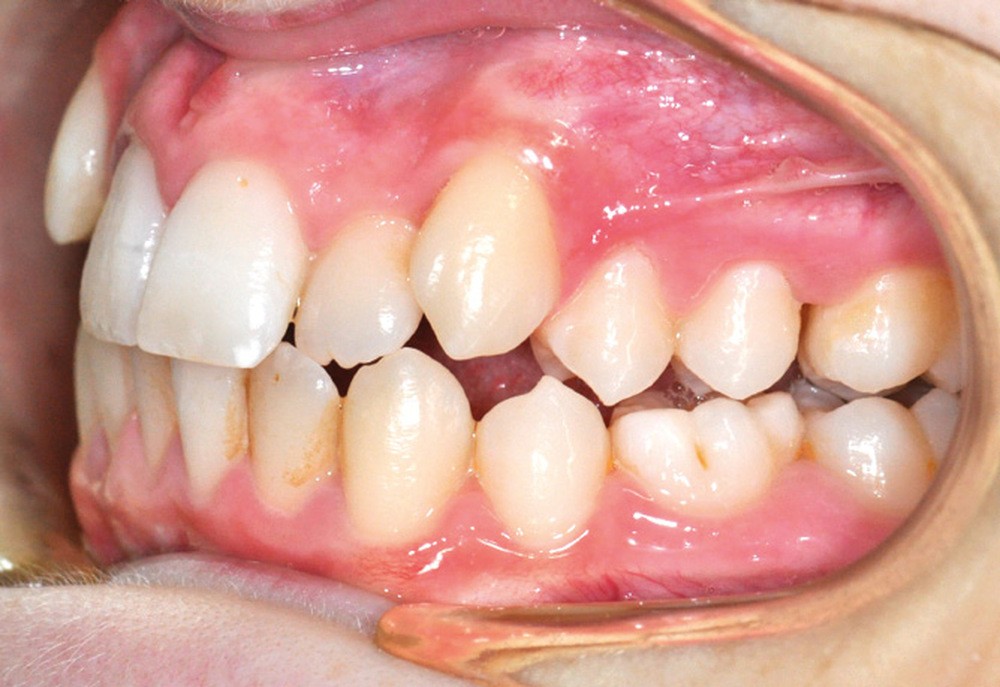

Julien nous consulte à l’âge de 11 ans et 4 mois pour des raisons essentiellement esthétiques, afin d’améliorer l’alignement de ses incisives maxillaires (fig. 1a-d) ; son chirurgien-dentiste l’a toutefois alerté sur un problème d’évolution des 35 et 47, dont l’inclusion a été mise en évidence lors d’un contrôle radiographique (fig. 1e).

L’examen intra-oral met en évidence une occlusion inversée bilatérale ainsi qu’un manque de place conséquent pour les incisives latérales maxillaires en palato-position et une infra-vestibulo-position de 13 et 23. Le patient est déjà en denture adulte jeune, hormis la persistance de la 75. L’occlusion est en classe II, plus marquée du côté droit sans engendrer de déviation des médianes incisives, d’où une mésio-position plus importante de la 13 par rapport à la 23.